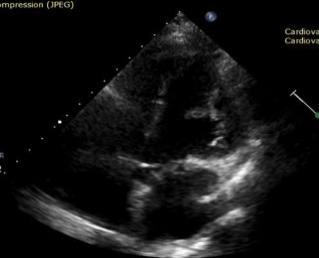

On a routine TTE follow-up, a highly mobile small mass attached to the anterolateral left ventricular wall was detected (Image.1 -2). Thrombus was the initial suspicion and the  patient was placed on oral anticoagulants and referred for further evaluation with cardiac magnetic resonance.

Image 1. 4Ch TTE of mass in LV and apex of RV